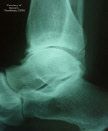

FOOT & ANKLE INJURIES

Foot and ankle emergencies happen every day. Broken bones, dislocations, sprains, contusions, infections, and other serious injuries can occur at any time. Early attention is vitally important. Whenever you sustain a foot or ankle injury, you should seek immediate treatment from a podiatric physician.